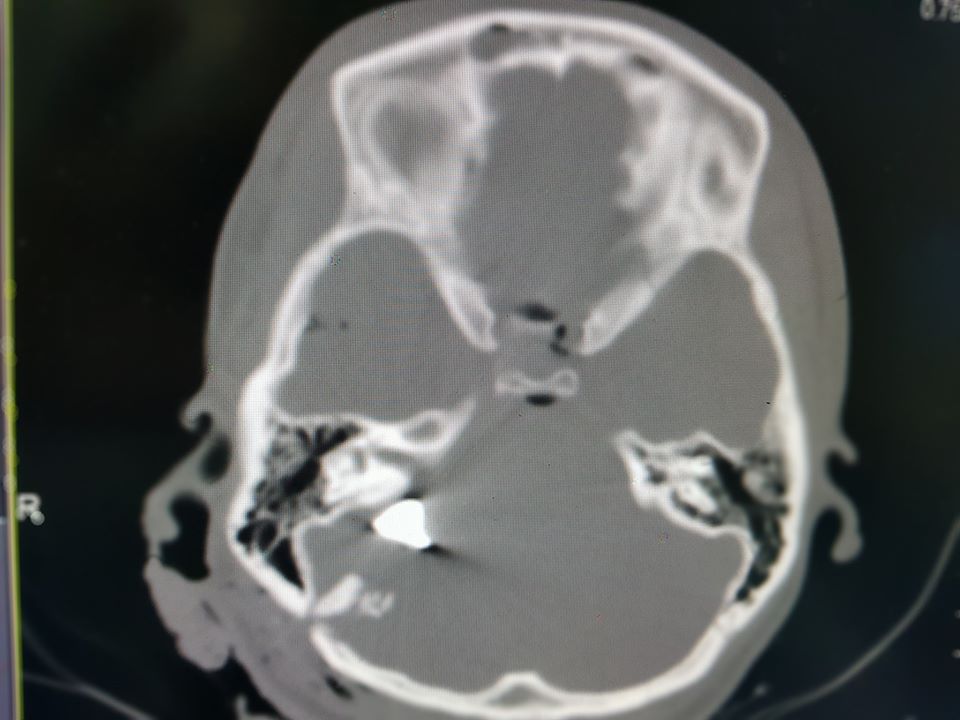

"Крайне тяжелое состояние, кома III степени, искусственная вентиляция легких и сверхвысокие дозы препаратов, поддерживающих артериальное давление. Взрывная черепно-мозговая травма, перелом костей свода и основания черепа, металлические обломки повредили жизненно важные участки мозга. Травма, не совместима с жизнью", - написал Толубаев.